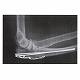

体内固定用ワイヤ テンションバンドピンシステム

●ワイヤーループに軟鋼線を通すことにより、骨折部の整復と確実なアンカーリングをもたらし、マイグレーションやバックアウトを防止します。

●ロープロファイルなワイヤーループは、、軟部組織への刺激と患者の不快感を最小限に抑えます。